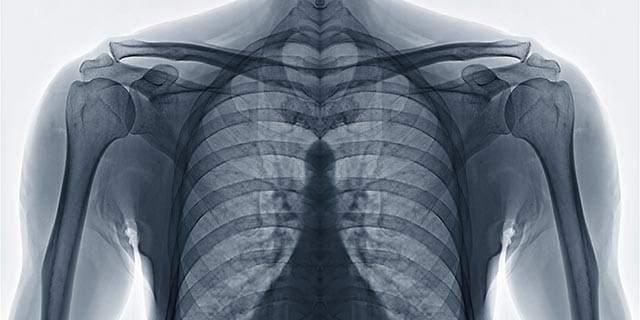

x-ray of chest wall

Chest Wall Surgery

Chest Wall Trauma and Rib Fractures

Chest wall trauma can be debilitating and painful. The UH Division of Thoracic and Esophageal Surgery offers care for all traumatic chest wall injuries (rib fracture, flail chest, sternal fracture). We have pioneered minimally invasive approaches and are using 3D printing and other novel techniques to improve healing and shorten recoveries.